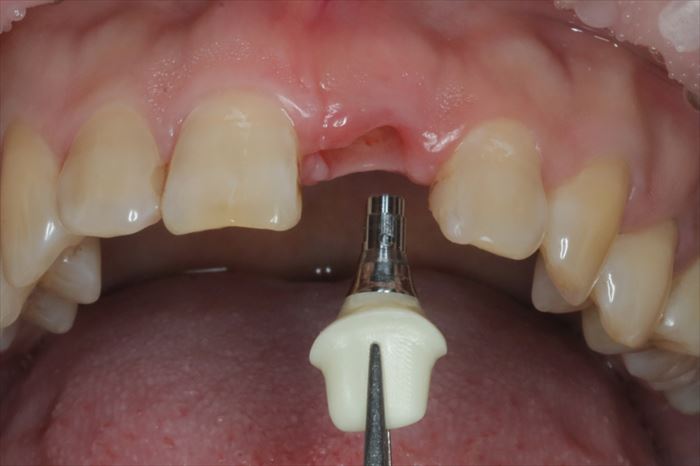

チタンベースにジルコニアを接着したジルコニアカスタムアバットメントを締結します。

ジルコニアカスタムアバットメントを締結しました。

アバットメントによって歯肉の形をマネージメントします。

本日は、慣れと咬み合わせの確認のため、プラスチック製の仮歯をセットします。